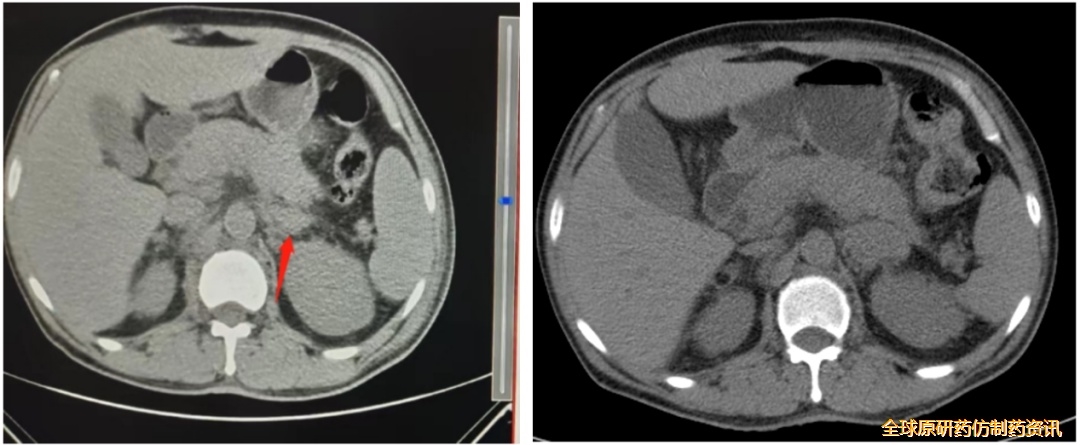

图5. 2022.06.28、2022.09.22胸腹盆CT平扫检查结果